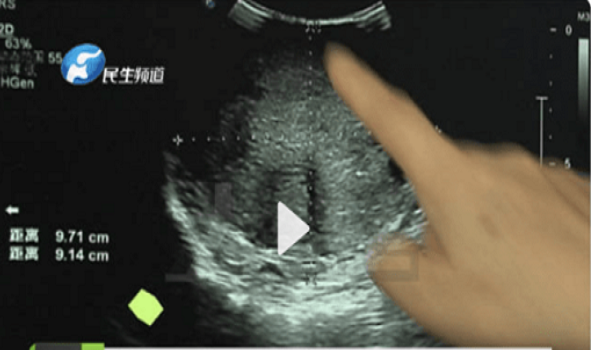

Mới đây, báo chí Trung Quốc đưa tin về việc một bé gái mới 15 tuổi mắc ung thư vú. Được biết, cô bé quê ở Hà Nam, hai bên ngực phát triển bất đối xứng rõ rệt. Thấy vậy, gia đình cho con đi khám thì bàng hoàng phát hiện bệnh nhân có khối u to hơn 10cm. Sự việc nhanh chóng thu hút sự chú ý, trở thành hot search trên Weibo.

| Bệnh nhân u vú ngày càng trẻ hóa. Nguyên nhân chủ yếu do lượng hormone và mất cân bằng trong chế độ ăn hàng ngày. Ảnh: Sohu. |